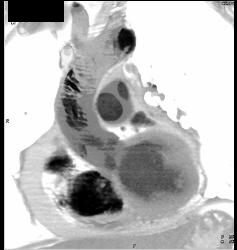

Diagnosis

Bicuspid Valve